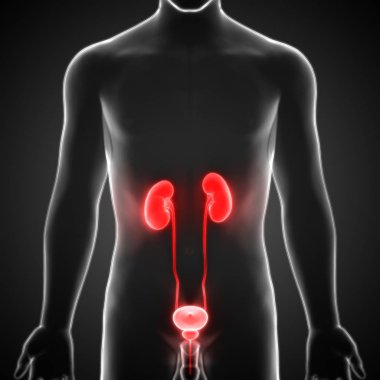

İnsan vücudundaki böbreklerin hologramı. Geleceğin sağlık hizmetleri. Modern tıp bilimi. 3B illüstrasyon, 3B canlandırma

ArkaplanresimlemeİnsanSağlıksağlıklıİlaçSağlık hizmetleriHastalıkTıbbidikkatteknolojiçizgi filmGeleceğe yönelikDoktorHastaneAygıtDijitalgövdeterapiTedavibiyolojiBilimkanserSistemGözlüklerAcıYenilikorgKulaklıktaşlaranatomiklinikİşlemOrgan nakliBöbreklerBöbrekHologramçokgenÜroloji3d oluşturma3B illüstrasyonpiyelonefritBenzer İçerikler